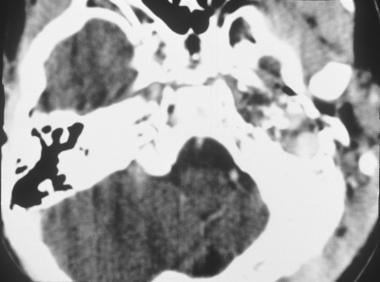

Rhabdomyosarcoma CT - Wikidoc

www.wikidoc.org

www.wikidoc.org

rhabdomyosarcoma ct wikidoc psoas muscle right heterogeneous ruslan mildly enlarged courtesy dr case source

Rhabdomyosarcoma CT - Wikidoc

www.wikidoc.org

www.wikidoc.org

rhabdomyosarcoma ct nasal wikidoc gif cavity radiopedia epistaxis